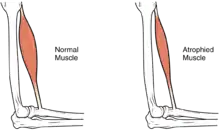

استفاده نادرست عضلانی ممکن است در دراز مدت، اثرات اضافه تری شامل آتروفی عضلانی را ایجاد کند. عدم تحرک ممکن است منجر به زخم بستر، بهخصوص در نواحی استخوانی گشته، که نیازمند اقدامات احتیاطی چون نرمتر کردن بستر و هر دو ساعت چرخش درون بستر جهت تخفیف فشار میباشد.[52] در دراز مدت، افرادی که از ویلچر استفاده میکنند، باید به صورت دوره ای جابجا شده تا فشار تخفیف یابد.[53] یکی از عوارض دیگر درد، شامل درد نوسیسپتیو (نشاندهنده آسیب بافتی بالقوه یا واقعیست) و درد نوروپاتی است، اینگونه عوارض هنگامی روی میدهند که اعصاب در غیاب محرکهای دردزا، تحت تأثیر انتقال پیامهای خطادار درد، قرار گیرند.[54] اسپاستیسیته، سفت کردن غیرقابل کنتر عضلات زیر سطح آسیبدیدگی است که در ۷۸–۶۵٪ از SCI مزمن رخ میدهد.[55] این رویداد ناشی از نقصان ورودی از مغز است که پاسخهای عضلانی رفلکسهای کششی را فرومینشاند.[56] این اسپاستیسیتهها با دارو و درمان فیزیکی قابل درمانند.[56] اسپاستیسیته، ریسک کنتراکچر (کوتاه شدن عضلات، زردپیها یا رباطها که ناشی از استفاده نشدن یکی از اندامهاست) را افزایش میدهد؛ میتوان از این مشکل با حرکات متعدد روزانهٔ اندام در محدوده کامل حرکتی اش، پیشگیری کرد.[57] یکی دیگر از مشکلات ناشی از عدم تحرک، از دست رفتن چگالی استخوان و تغییرات بافت استخوانیست.[58][59] از دست رفتن چگالی استخوان (کانیزدایی استخوان) را ناشی از نقصان ورودی از سوی عضلات فلج یا ضعیف شده میدانند که میتواند منجر به افزایش ریسک شکستگیها گردد.[60] برعکس، پدیده استخوانسازی نابجا (heterotopic ossification)، که رشد بیش از حد بافت استخوانی در نواحی بافت نرم است، به خوبی شناخته نشده.[61] این پدیده در سطح زیر آسیب دیدگی رخ داده، احتمالاً ناشی از التهاب بوده و در ۲۷٪ از افراد به مرحله ای میرسد که از نظر بالینی قابل توجه میشود.[61]